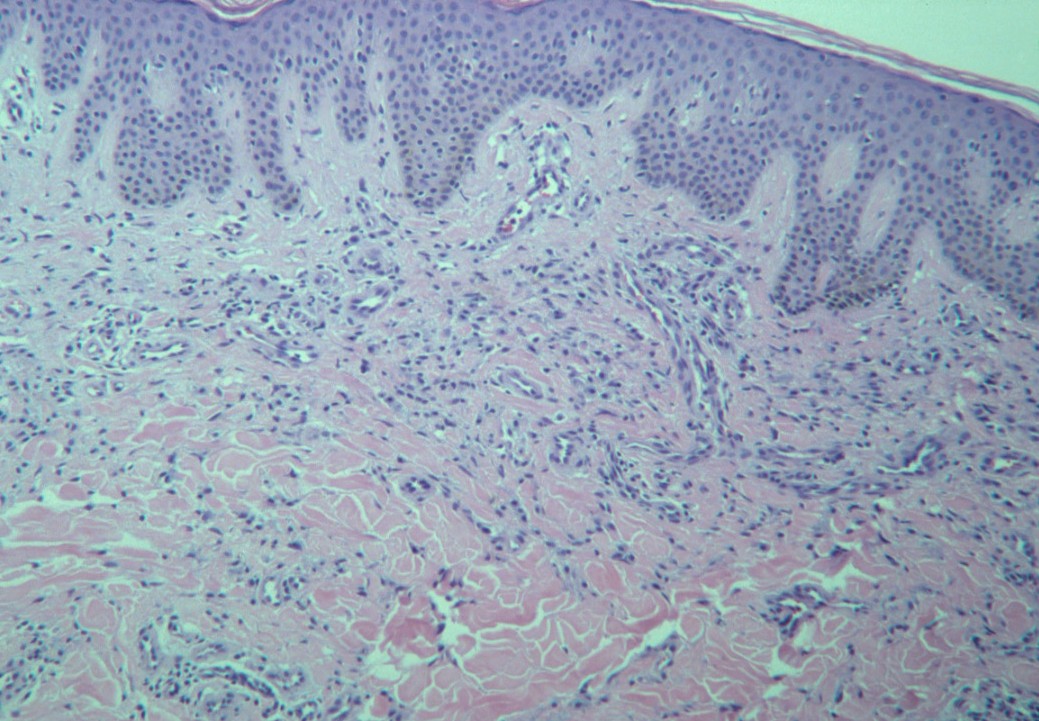

mastocytose